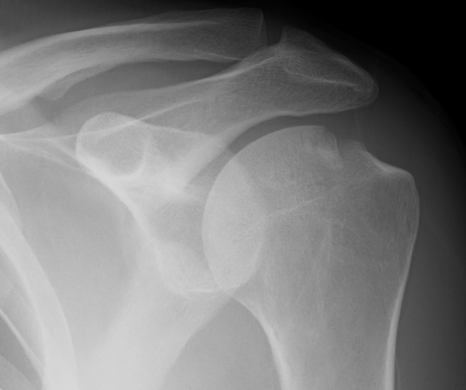

Xray

Bony bankart

Hill Sachs